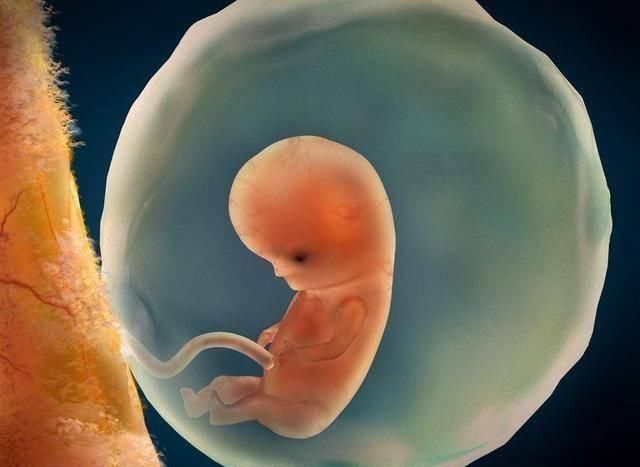

文章插图

3、胎芽

很多朋友认为胎芽是胎儿身上的芽,其实不是,它指的是“胎儿本身”怀孕6周的时候,胚胎像松子仁难么大,但是原始器官、四肢雏形已经形成,医学上称它为“胎芽”。身体蜷缩成大“C”字,也很像一个芽。